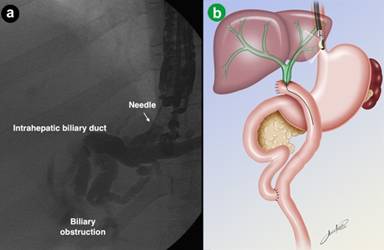

The left intrahepatic duct was visualized using a linear echoendoscope (GF-UCT140AL5, Olympus America, Melville, NY, USA) placed in the remnant stomach. The dilated left intrahepatic duct was punctured, in a transhepatic approach, with a 19-gauge FNA needle (EUSN-19-T, Cook Medical, Bloomington, IN, USA) through the gastric wall after using Doppler to avoid any intervening vessels. Bile was aspirated and contrast was injected to demonstrate biliary opacification. A dilated left intrahepatic duct, with a severe stenosis in the hepatico-jejunal anastomosis was observed (Figure 1).

|

Figure 1. a. EUS-guided extrahepatic biliary puncture: cholangiography showing abrupt stop in the biliary tree corresponding to stenosis of the anastomosis. b. Schematic picture showing the EUS-guided puncture of intrahepatic biliary dilatation and the placement of the guidewire. |